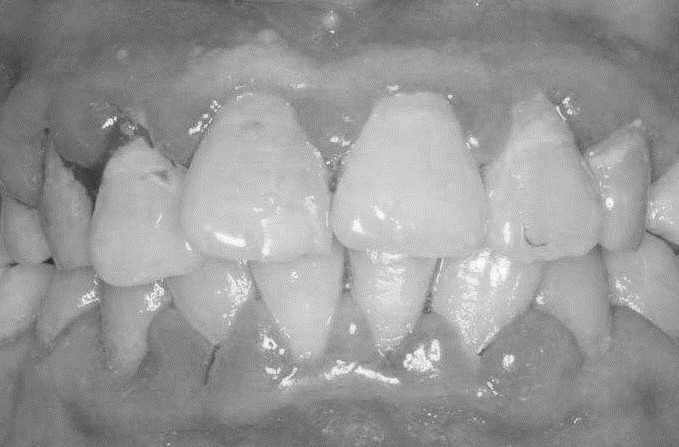

牙龈肥大病史采集6大要点及可能的6种疾病诊断

2021-04-30